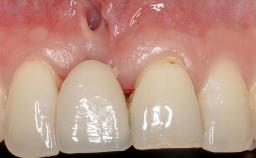

A 30-year-old woman was referred by her general dentist for evaluation of an esthetic complication related to previous implant treatment for congenitally missing maxillary lateral incisors. The patient’s chief complaint was the inadequate esthetic appearance of her smile. The case demonstrates the use of a combined approach to achieve optimal results. Two different flap designs - a tunnel technique and a coronally advanced flap - are employed based on the surgical objectives for the affected site.